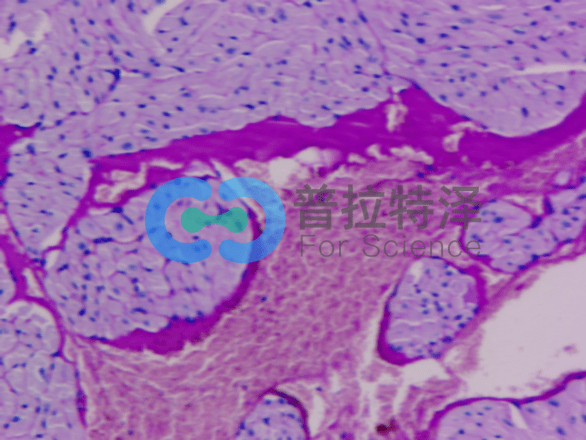

答:PAS染色,全稱周期性酸-希夫染色,是一種在組織學中廣泛應用的染色方法。它的主要目的是檢測組織中的糖類物質。在染色過程中,周期性酸發揮了關鍵作用,它能夠將糖類物質中相鄰的兩個碳原子上的羥基氧化成醛基。隨后,希夫試劑與醛基發生反應,使糖類物質呈現出獨特的紫紅色。這種染色方法不僅有助于我們觀察糖類的分布和形態,還為研究糖類的生物功能提供了重要的線索。

相比之下,MPO染色則是一種用于檢測白細胞中過氧化物酶(MPO)存在和活性的實驗技術。MPO是一種在白細胞中廣泛存在的酶,它參與了細胞內外的氧化還原反應。MPO的存在和活性與許多疾病的發生和發展密切相關,如心血管疾病、炎癥性疾病以及腫瘤等。因此,MPO染色在醫學研究和臨床診斷中具有極其重要的意義。在染色過程中,通過特定的染色劑和反應條件,可以觀察到MPO在白細胞中的分布和活性水平,從而為疾病的診斷和治療提供依據。

→PAS染色主要用于檢測和鑒定組織或細胞內的多糖和糖蛋白。

→PAS染色可以顯示細胞或組織中的糖原、粘附物、酸性黏多糖、肝細胞中的糖原顆粒等。

→MPO染色主要用于檢測和鑒定組織或細胞中的髓過氧化物酶,這是嗜中性粒細胞的特異標記。

→MPO染色常用于血液或組織切片中,以確定白細胞浸潤情況,尤其是嗜中性粒細胞。